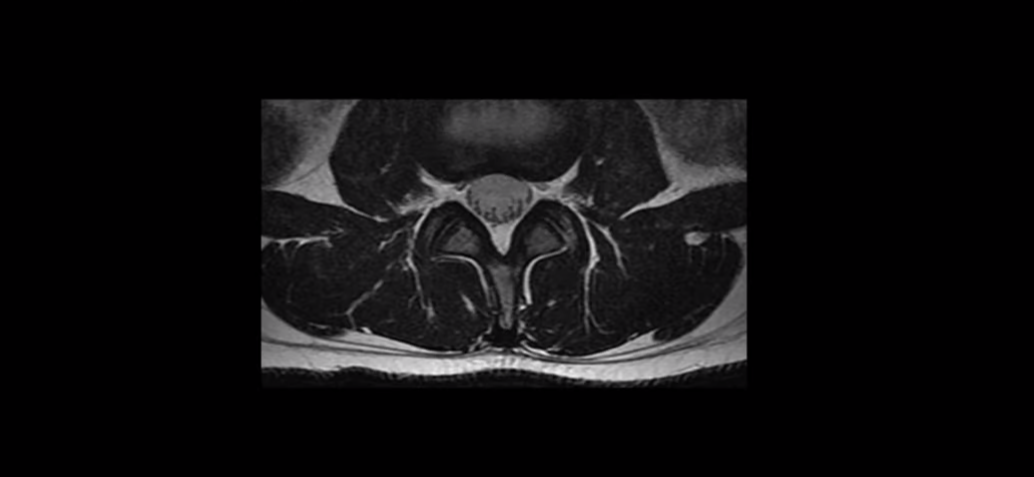

나이가 들면서 척추가 노화와 퇴행에 여기 신경 구멍이 좁아지는 걸 협착이라고 하는데, 그래서 협착증은 대부분 60대 이후에 발병합니다.

그런데 나이가 들면 이 척추관만 노화되겠습니까? 주변에 있는 근육들도 다 늙게 됩니다. 즉 협착증이라는 병은 늙어서 척추와 근육이 다 무너진 것입니다. 나이가 들면 근육이 많이 줄어들고 약해지고, 고령으로 갈수록 근육은 더 심하게 망가집니다. 이런 약해진 근육으로 일을 하고 또 운동을 하게 되면 근육이 뭉치고 굳어버리고 허리를 잘 지탱하지 못하게 되니까 척추가 다 뒤틀리게 되는데, 이렇게 근육이 줄어들고 약해지고 문제가 생겨서 잘 허리를 지지하지 못하니까 신경이 더 눌리고, 협착증이 더 악화되게 되는 겁니다.

결국 협착증의 원인은 신경 구멍이 좁아진 것만이 아니라 근육도 같이 무너진 것입니다. 아직도 많은 환자분들이 본인 근육에 문제가 있다는 생각은 못하고, 신경 구멍이 좁아진 것만이 문제라고 생각해서 신경주사만 맞고 있습니다. 그런데 협착증이 아직 심하지 않은 초기일 때는 신경주사를 맞아서 신경에 생긴 염증이 좀 줄어들면 증상이 좋아질 수 있지만, 시간이 지나 근육이 점점 더 줄어들고 약해지면서 심하게 뭉치고 망가지면 결국 신경주사 효과도 없어지게 됩니다. 주사치료가 효과가 없으면 이제 수술로 신경 구멍을 뚫어줘야 한다는 말을 듣게 되는데, 계속 반복해서 말하지만 협착증은 신경 구멍도 좁아지고 근육도 다 망가진 것이기 때문에 굳이 수술을 하지 않아도 근육재활치료를 통해 근육 상태만 많이 좋아져도 신경 눌림이 훨씬 더 줄어들고, 그러면 방사통도 좋아지고 다리 힘도 더 들어가서 더 힘차게 잘 걸을 수 있게 됩니다. 이에 대한 자세한 내용은 아래 영상을 보시길 바랍니다.